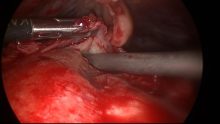

Through the Keyhole…

Veterinary Small Animal Laparoscopy CPD We held our second veterinary laparoscopy course in January with 12 visiting delegates. All ...